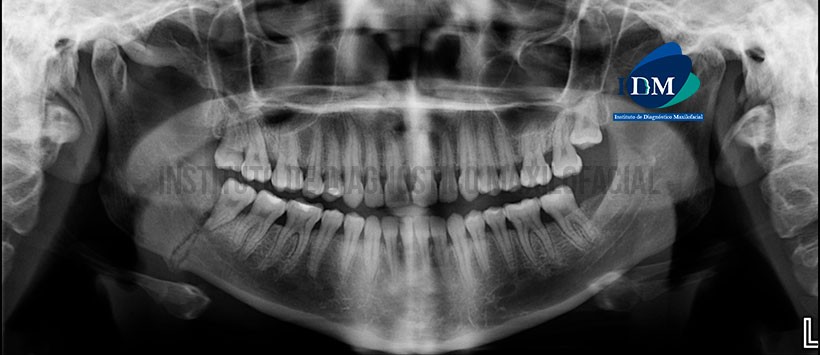

A la evaluación de la radiografía panorámica se aprecia una alteración de la morfología de cóndilo mandibular derecho (variante anatómica), neumatización alveolar de ambos senos maxilares, apiñamiento dentario de sector anterior, placa mineralizada en zona cervical de todo el sector dentario y múltiples restauraciones. Siendo lo mas resaltante la presencia de dos trazos radiolúcidos oblicuos, localizados en zona antegonial de lado derecho. (Figura 1)

A la evaluación mediante la tomografía volumétrica de haz cónico, se confirma que dichos trazos comprometen ambas tablas óseas (vestibular y palatina), la basal mandibular y hueso medular. Así mismo presenta una extensión desde la basal mandibular hacia cima de reborde alveolar (por distal de la pieza 48), adicionalmente se evidencia una aposición ósea en ambas tablas. Finalmente se visualiza que solo compromete las corticales del conducto dentario inferior. (Figura 2, Figura 3 y Figura 4)

En las reconstrucciones 3D y reformación panoramica podemos visualizar de manera ilustrativa las estructuras previamente descritas. (Figura 5, Figura 6 y Figura 7)

- Fractura mandibular en zona antegonial en proceso de reparación ósea